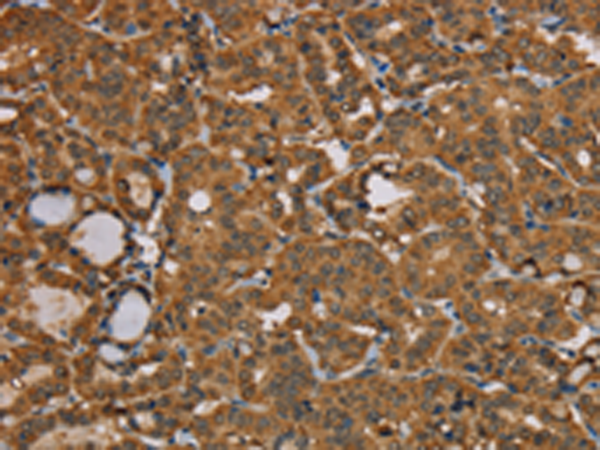

分类: 科研抗体货号: P08540别名: NOS2; ZC2HC12B应用: IHC反应种属: Human